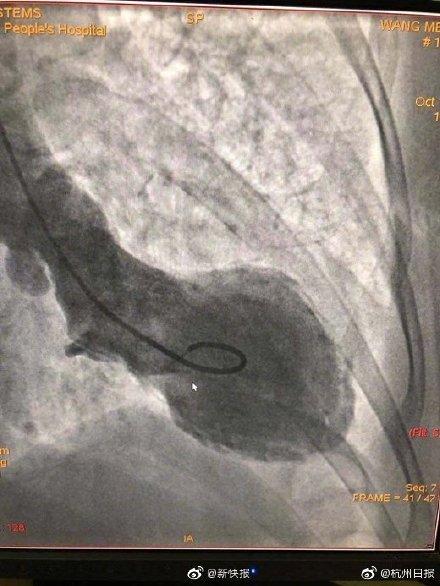

#光明网#女子吵架后突然心碎!医生:中年女性更易“心碎”。【女子吵架后突然心碎!医生:中年女性更易“心碎”】近日 , 杭州一名40多岁的女子因琐事与邻居大吵一架 , 双方势均力敌 , 但要强的女子认为没占上风就是吃亏 , 为此愤愤不平 , 气得发抖 。 不久后她突发持续胸痛胸闷 , 几个小时都不能缓解 , 家人忙将其送往医院急诊 , 最后被诊断为“心碎综合征” 。 医生表示 , 中年女性更容易“心碎” , 而年轻女性“心碎”或多因感情因素引起 。 (杭州日报)